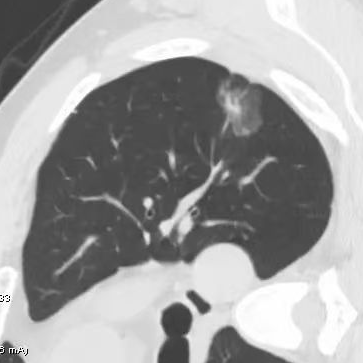

健康直通车: 健康是生命的宝贵财富,也是幸福生活的基石。为了更好地服务广大百姓,传播健康知识,葫芦岛市第二人民医院推出“健康直通车”专题栏目,将专业的医学知识以通俗易懂的方式传递给每一位市民,掌握科学的疾病预防方法,共同构筑健康中国的坚实基石。 什么是肺结节 肺结节是指肺内直径小于或等于3cm的类圆形或不规则形病灶,影像学表现为密度增高的阴影。大于3cm的称肿块。肺结节依其密度不同可分为实性结节、部分实性结节、磨玻璃结节,其中部分实性结节的恶性可能性最大,磨玻璃结节次之,实性结节尤其是小的实性结节结节最可能是良性的。 肺结节的常见病因 1、良性(约90%) 🔸 感染:结核、真菌、细菌性肺炎后遗留的瘢痕; 🔸 非感染:错构瘤(良性肿瘤)、炎性假瘤、血管瘤等。 2、恶性(约10%) 🔸原发性肺癌(如腺癌、鳞癌); 🔸转移性肿瘤(其他器官癌症转移至肺)。 如何根据影像判断肺结节性质 1、依据结节大小判断 🔸小于0.5cm的肺结节绝大多数都是良性的,属于微小结节。即使部分小于0.5cm肺结节是恶性的,但是适当的观察不影响预后。每年复查一次胸部CT就可以。 🔸大于0.5cm持续存在的纯磨玻璃结节,观察6个月,若持续存在,不管有无进展均多数是恶性的,视患者意愿,手术可以立即做也可观察至进展再做,不影响预后。 🔸大于0.8cm的部分实性结节恶性可能性非常大,应积极评估结节边缘毛刺、分叶、胸膜凹陷等征象。 🔸若实性部分大于0.5cm,恶性率显著提高。若在3~6个月随访期间实性部分增大或者总体部分增大,都可以考虑手术切除。而即使小于0.8cm的部分实性结节也需3个月就复查对比。 2、依据肺结节形态 如CT上提示病灶形态不规则、毛刺、分叶、胸膜凹陷、空泡征、血管集束征等,符合恶性肿瘤的征象。 🔸结节与正常肺组织之间界限非常清楚的恶性可能性大。 🔸结节密度不均呈混杂密度或均匀较大纯磨玻璃结节也基本是恶性的。 🔸有胸膜牵拉(不管是肺表面的脏层胸膜还是叶间裂部位的胸膜)的恶性可能性大。 🔸结节有浅分叶、细毛刺,密度较高而与周围肺组织边界不清的恶性可能性大。 🔸磨玻璃或混合磨玻璃结节存在小空洞的恶性可能性大。 🔸影像上似慢性炎表现,而没有炎症相关的其他异常,特别当所谓炎症区域内部或一侧与正常肺组织之间界限非常清楚的基本上是恶性的。 3、从结节发展情况来看 所有随访中增大进展的都需要考虑恶性可能,不进展而持续存在的纯磨玻璃结节也需考虑恶性。 葫芦岛市第二人民医院肺结节诊治中心孙振教授深耕肺结节领域四十余载,凭借对临床实践的执着钻研与深厚积淀,在肺结节精准诊断及鉴别诊断领域形成独到见解。他系统总结海量临床病例,创新性提炼出一套科学化、规范化的肺结节全周期诊疗体系,尤其在早期微小结节的影像特征识别、良恶性风险分层等方面积累了丰富经验,为众多患者提供了精准、高效的诊疗方案。 人民医院·人民名医 孙振 主任医师 三级教授 ·葫芦岛市第二人民医院胸外科主任、肺结节诊治中心主任 ·中国医科大学客座教授 ·原央企总医院著名胸外科专家 ·辽宁省医学会胸外科委员 ·辽宁省抗癌协会肺癌专业委员会委员 ·辽宁省细胞生物学学会食管癌专业委员会理事 ·主持多项科研成果获科技成果奖、科技进步奖、国家专科奖项 医学成就 从事胸外科临床工作近40年,担任胸外科首席专家及科室主任20余年,是我省胸外科领军人物,推动肺癌、食管癌等胸部肿瘤外科的规范化诊疗,在央企总医院牵头成立了肺结节诊疗中心,率先开展CT引导下肺内小结节定位切除,既确切完整切除肺内小结节,又降低肺功能损害。 专业特色 擅长肺癌、食管癌的外科手术和综合治疗,在各类高难度胸外伤手术治疗、胸腔镜微创手术、胸腺瘤手术及复杂并发症处理方面具有高深造诣,尤其擅长肺癌早期诊断,胸部小结节CT早期肺癌的鉴别等。完成各类高难度胸外科手术5000余例,其中微创手术占比达90%,治愈率达98%,多项业务填补省内空白。 开展的高难手术 胸腔镜肺部结节微创手术、肺癌根治术、食管癌根治术、各种纵隔肿瘤切除术、胸骨后甲状腺手术及胸部复合性外伤的抢救手术等。